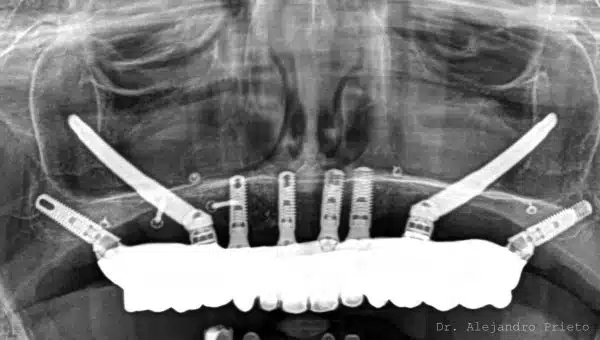

Implantes pterigoideos: antes y después

Los implantes pterigoideos permiten pasar de una situación de edentulismo o prótesis inestables a dientes fijos, incluso en pacientes con atrofia ósea severa.

A continuación se muestran casos reales de implantes pterigoideos antes y después, donde se aprecia la mejora funcional y estética.

En Dr. Alejandro Prieto Dental somos especialistas en rehabilitaciones de boca completa con implantes

El equipo está liderado por el Dr. Alejandro Prieto, cirujano implantólogo de prestigio internacional, experto en impantes de boca completa y en resultados de alta estética dental. Contamos con laboratorio dental en exclusiva, lo que nos permite controlar internamente cada fase del tratamiento para asegurar calidad, precisión y resultados predecibles.